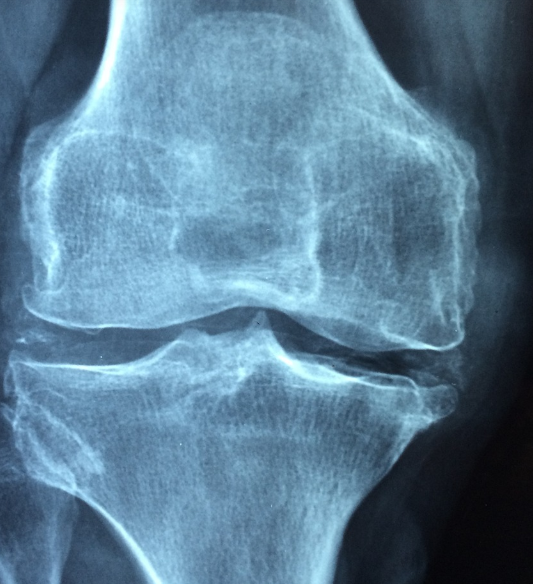

- 척추뼈, 손목, 고관절 골절 위험 증가